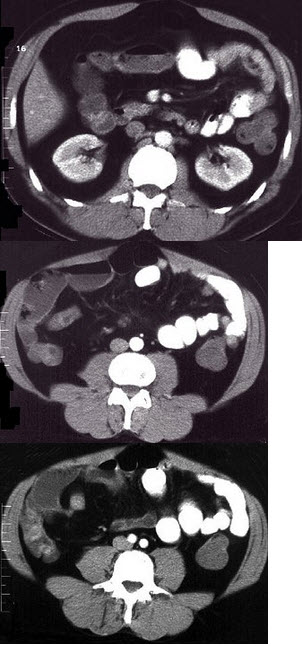

女,30岁,右下腹痛,腹泻便秘交替出现,消瘦乏力,血沉加快,X线检查如图,最佳的诊断是( )

A:小肠癌

B:小肠结核

C:小肠克罗恩病

D:结肠癌

E:阑尾炎